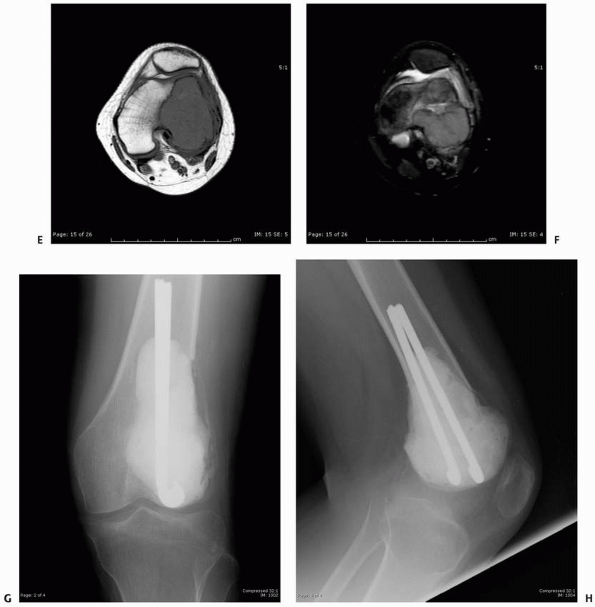

![]() |

FIGURE 6-11 (continued)

The patient then underwent biopsy confirming the diagnosis, followed by curettage and bone grafting. Four months postoperatively (E,F) the lesion is completely healed and the patient resumed normal physical activities. (Figures reproduced with permission from The Childrens Orthopaedic Center, Los Angeles, CA.) |

A 15-year-old girl presented with several months history of progressive left knee pain and recent inability to bear weight. On initial radiographs (A,B) there is a nondisplaced pathologic fracture (arrow) through a well-defined, lytic, eccentric, epiphyseal lesion of the distal femur. There is some bone expansion and metaphyseal extension. MR T1-weighted (C,E) and T2-weighted (D,F), coronal (C,D), |

FIGURE 6-12 (continued) and axial (E,F)

images better define the extent of bone and surrounding soft tissue involvement and the presence of cortical disruption. The patient underwent tissue confirmation of giant cell tumor and extended intralesional resection with cryosurgery, cementation, and Rush rod instrumentation (G,H). (Figures reproduced with permission from The Childrens Orthopaedic Center, Los Angeles, CA.) |